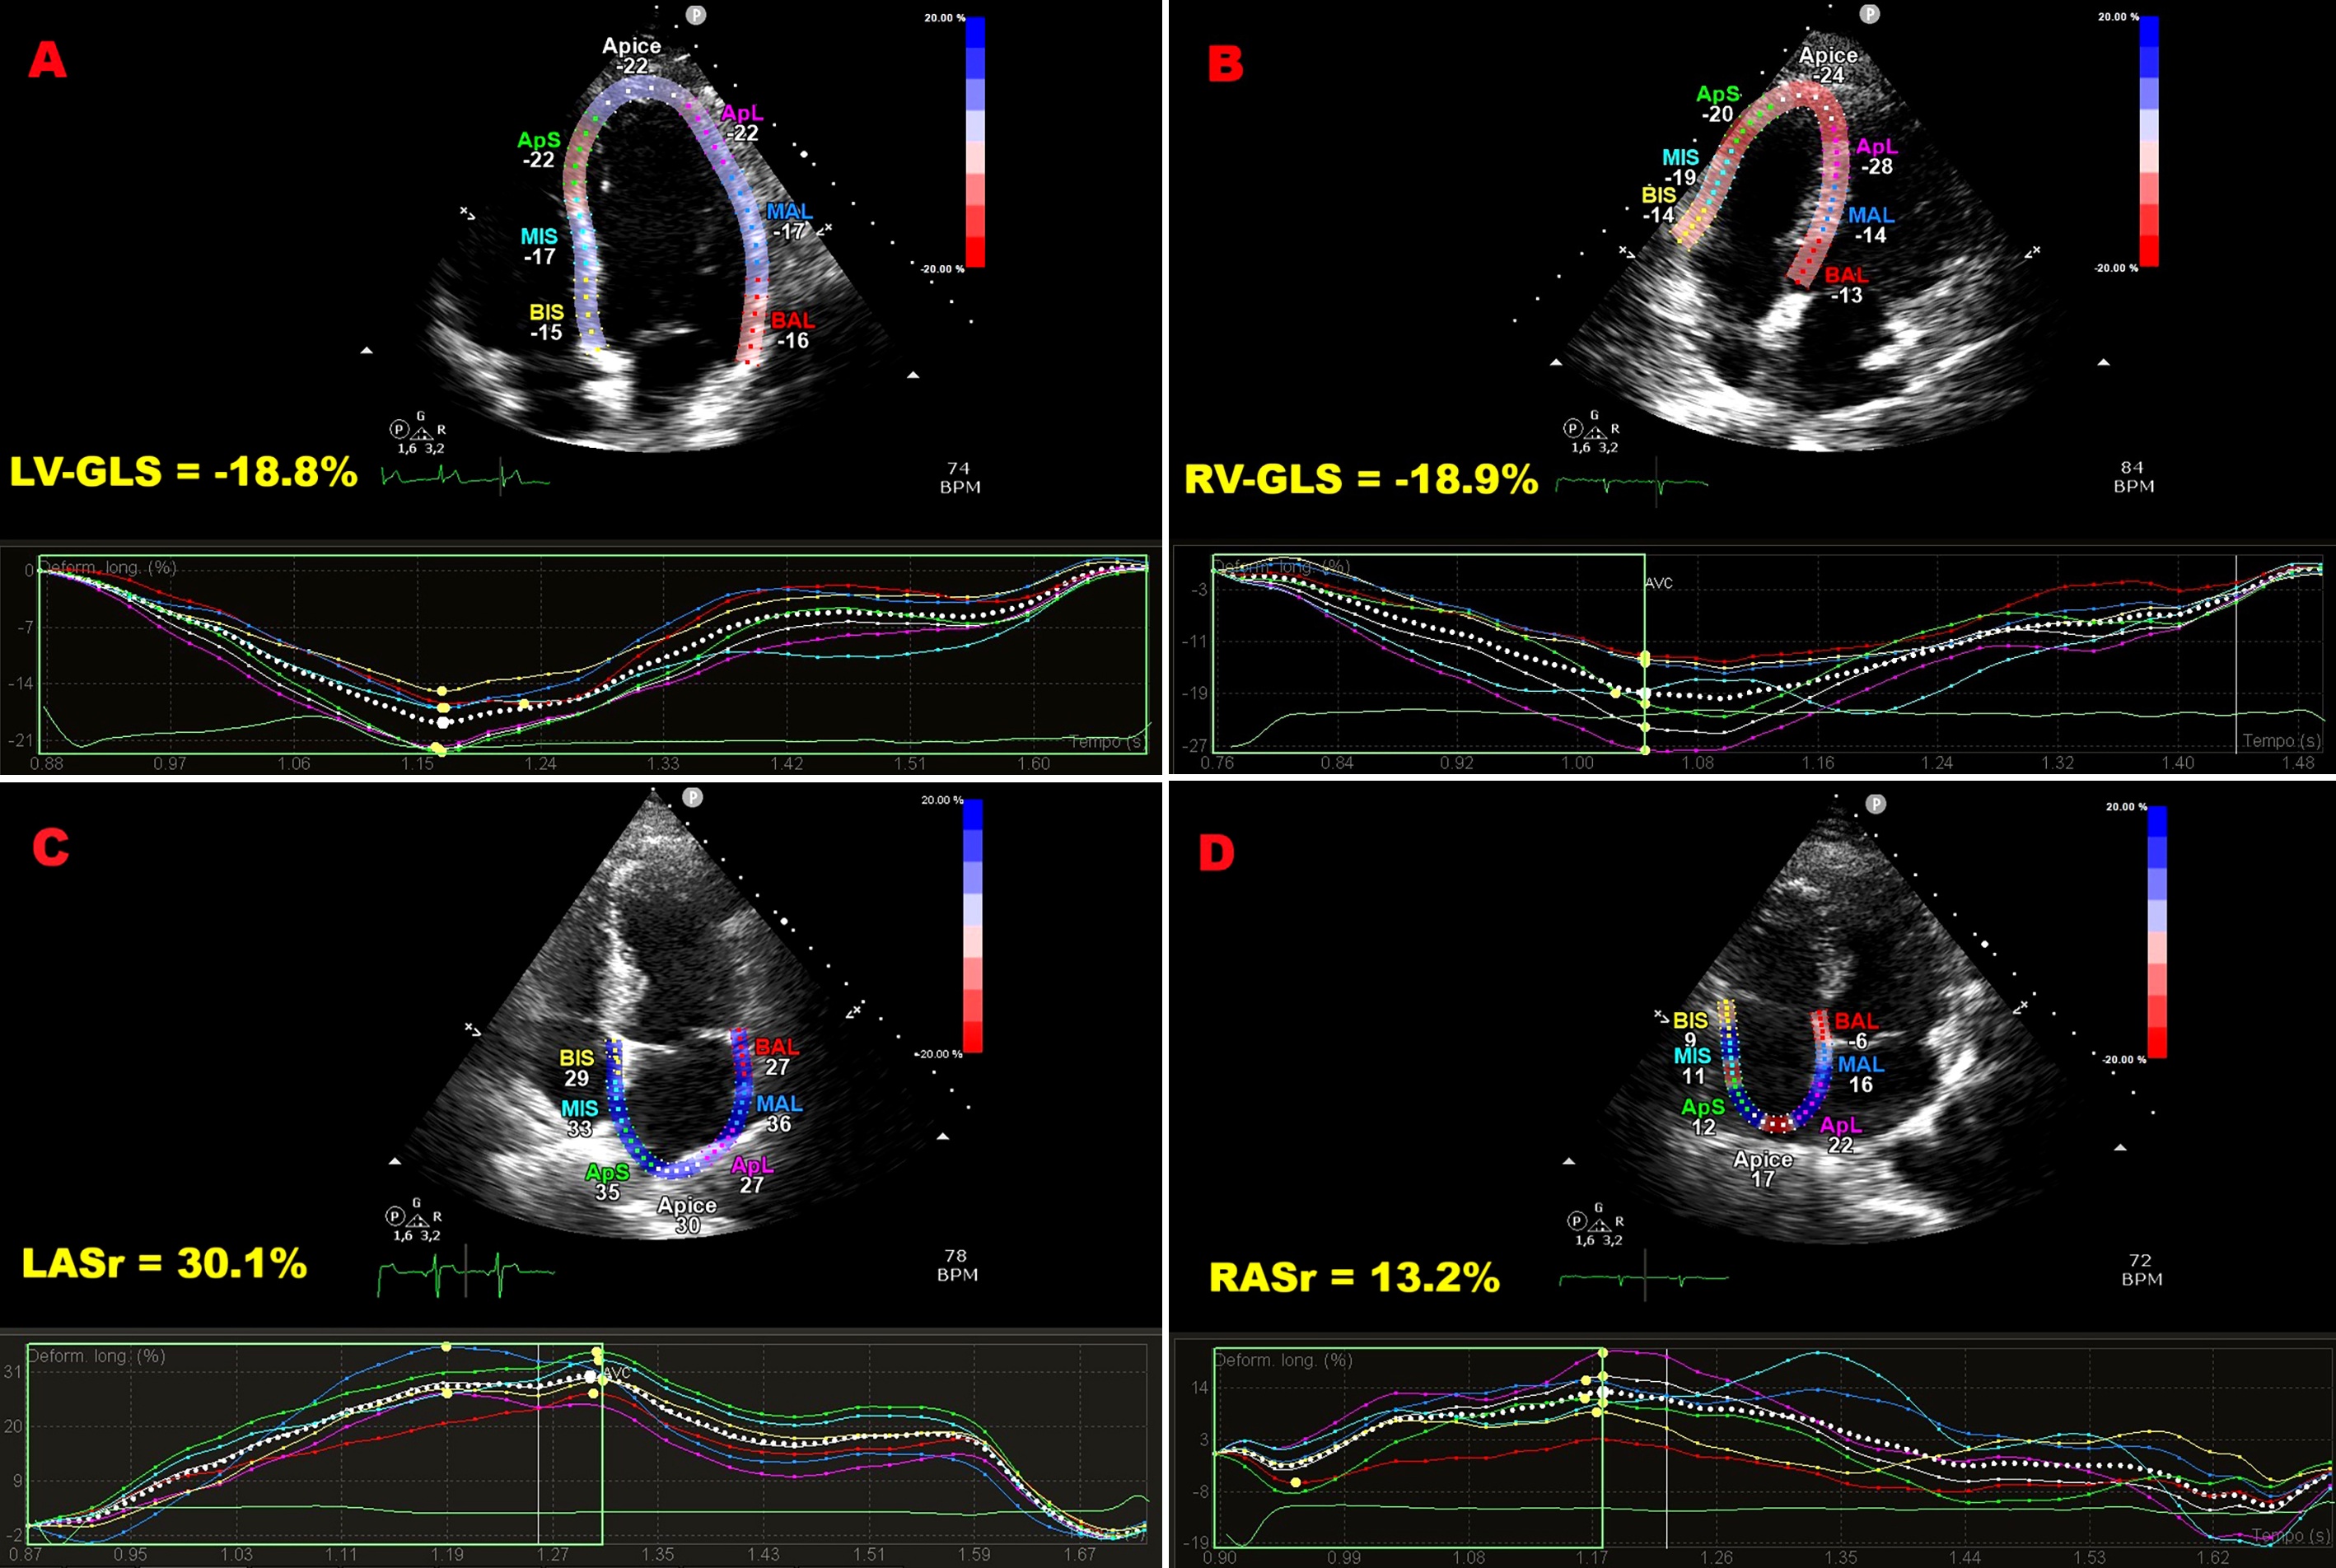

Background: Speckle-tracking echocardiography (STE) has been increasingly used to uncover subtle cardiac dysfunction in patients with extracardiac sarcoidosis (ECS) who show no clinical evidence of heart disease. However, prior investigations were mostly retrospective, methodologically heterogeneous, and focused primarily on left ventricular (LV) function. We conducted a prospective study to provide a broader evaluation of myocardial deformation across both ventricles and atria in non-fibrotic ECS. Methods: Forty-one patients with non-fibrotic ECS (mean age 57.4±10.2 years; 58.5% male) and 30 age- and sex-matched healthy controls (58.5±11.1 years; 53.3% male) were enrolled. All participants underwent conventional transthoracic echocardiography (TTE) supplemented by comprehensive STE analysis of ventricular and atrial function. Subclinical myocardial dysfunction was defined as LV global longitudinal strain (GLS) less negative than –20%, and potential predictors were analyzed. Results: Standard TTE excluded infiltrative cardiomyopathy but revealed higher E/average e′ ratios in the ECS group, suggesting subtle diastolic dysfunction. While traditional indices of biventricular systolic function remained preserved, STE demonstrated significant reductions in LV-GLS, LV global circumferential strain, right ventricular-GLS, and both left and right atrial reservoir strain. Multivariate analysis identified disease duration as the sole independent determinant of LV-GLS impairment (OR 2.26, 95%CI 1.10–4.65; p=0.03). A disease duration of ≥4.5 years predicted abnormal GLS with 88% sensitivity and 75% specificity (AUC 0.89; 95%CI 0.76–1.00). Conclusions: Non-fibrotic ECS is associated with early impairment of biventricular and biatrial strain despite preserved conventional function. The extent of dysfunction correlates strongly with disease duration, underscoring the value of STE for early detection and monitoring. Figure 1. Illustrative example of LV-GLS (A), RV-GLS (B), LASr (C) and RASr (D) assessment by speckle tracking echocardiography in an ECS patient participating in the present study. Figure 2. Bull’s eye plots derived from 2D-STE illustrating LV-GLS and LV-GCS in an ECS patient (A and C, respectively) and in a healthy control (B and D, respectively). Figure 3. ROC curve analysis performed to determine the optimal cutoff for disease duration in predicting impaired LV-GLS within the ECS cohort.